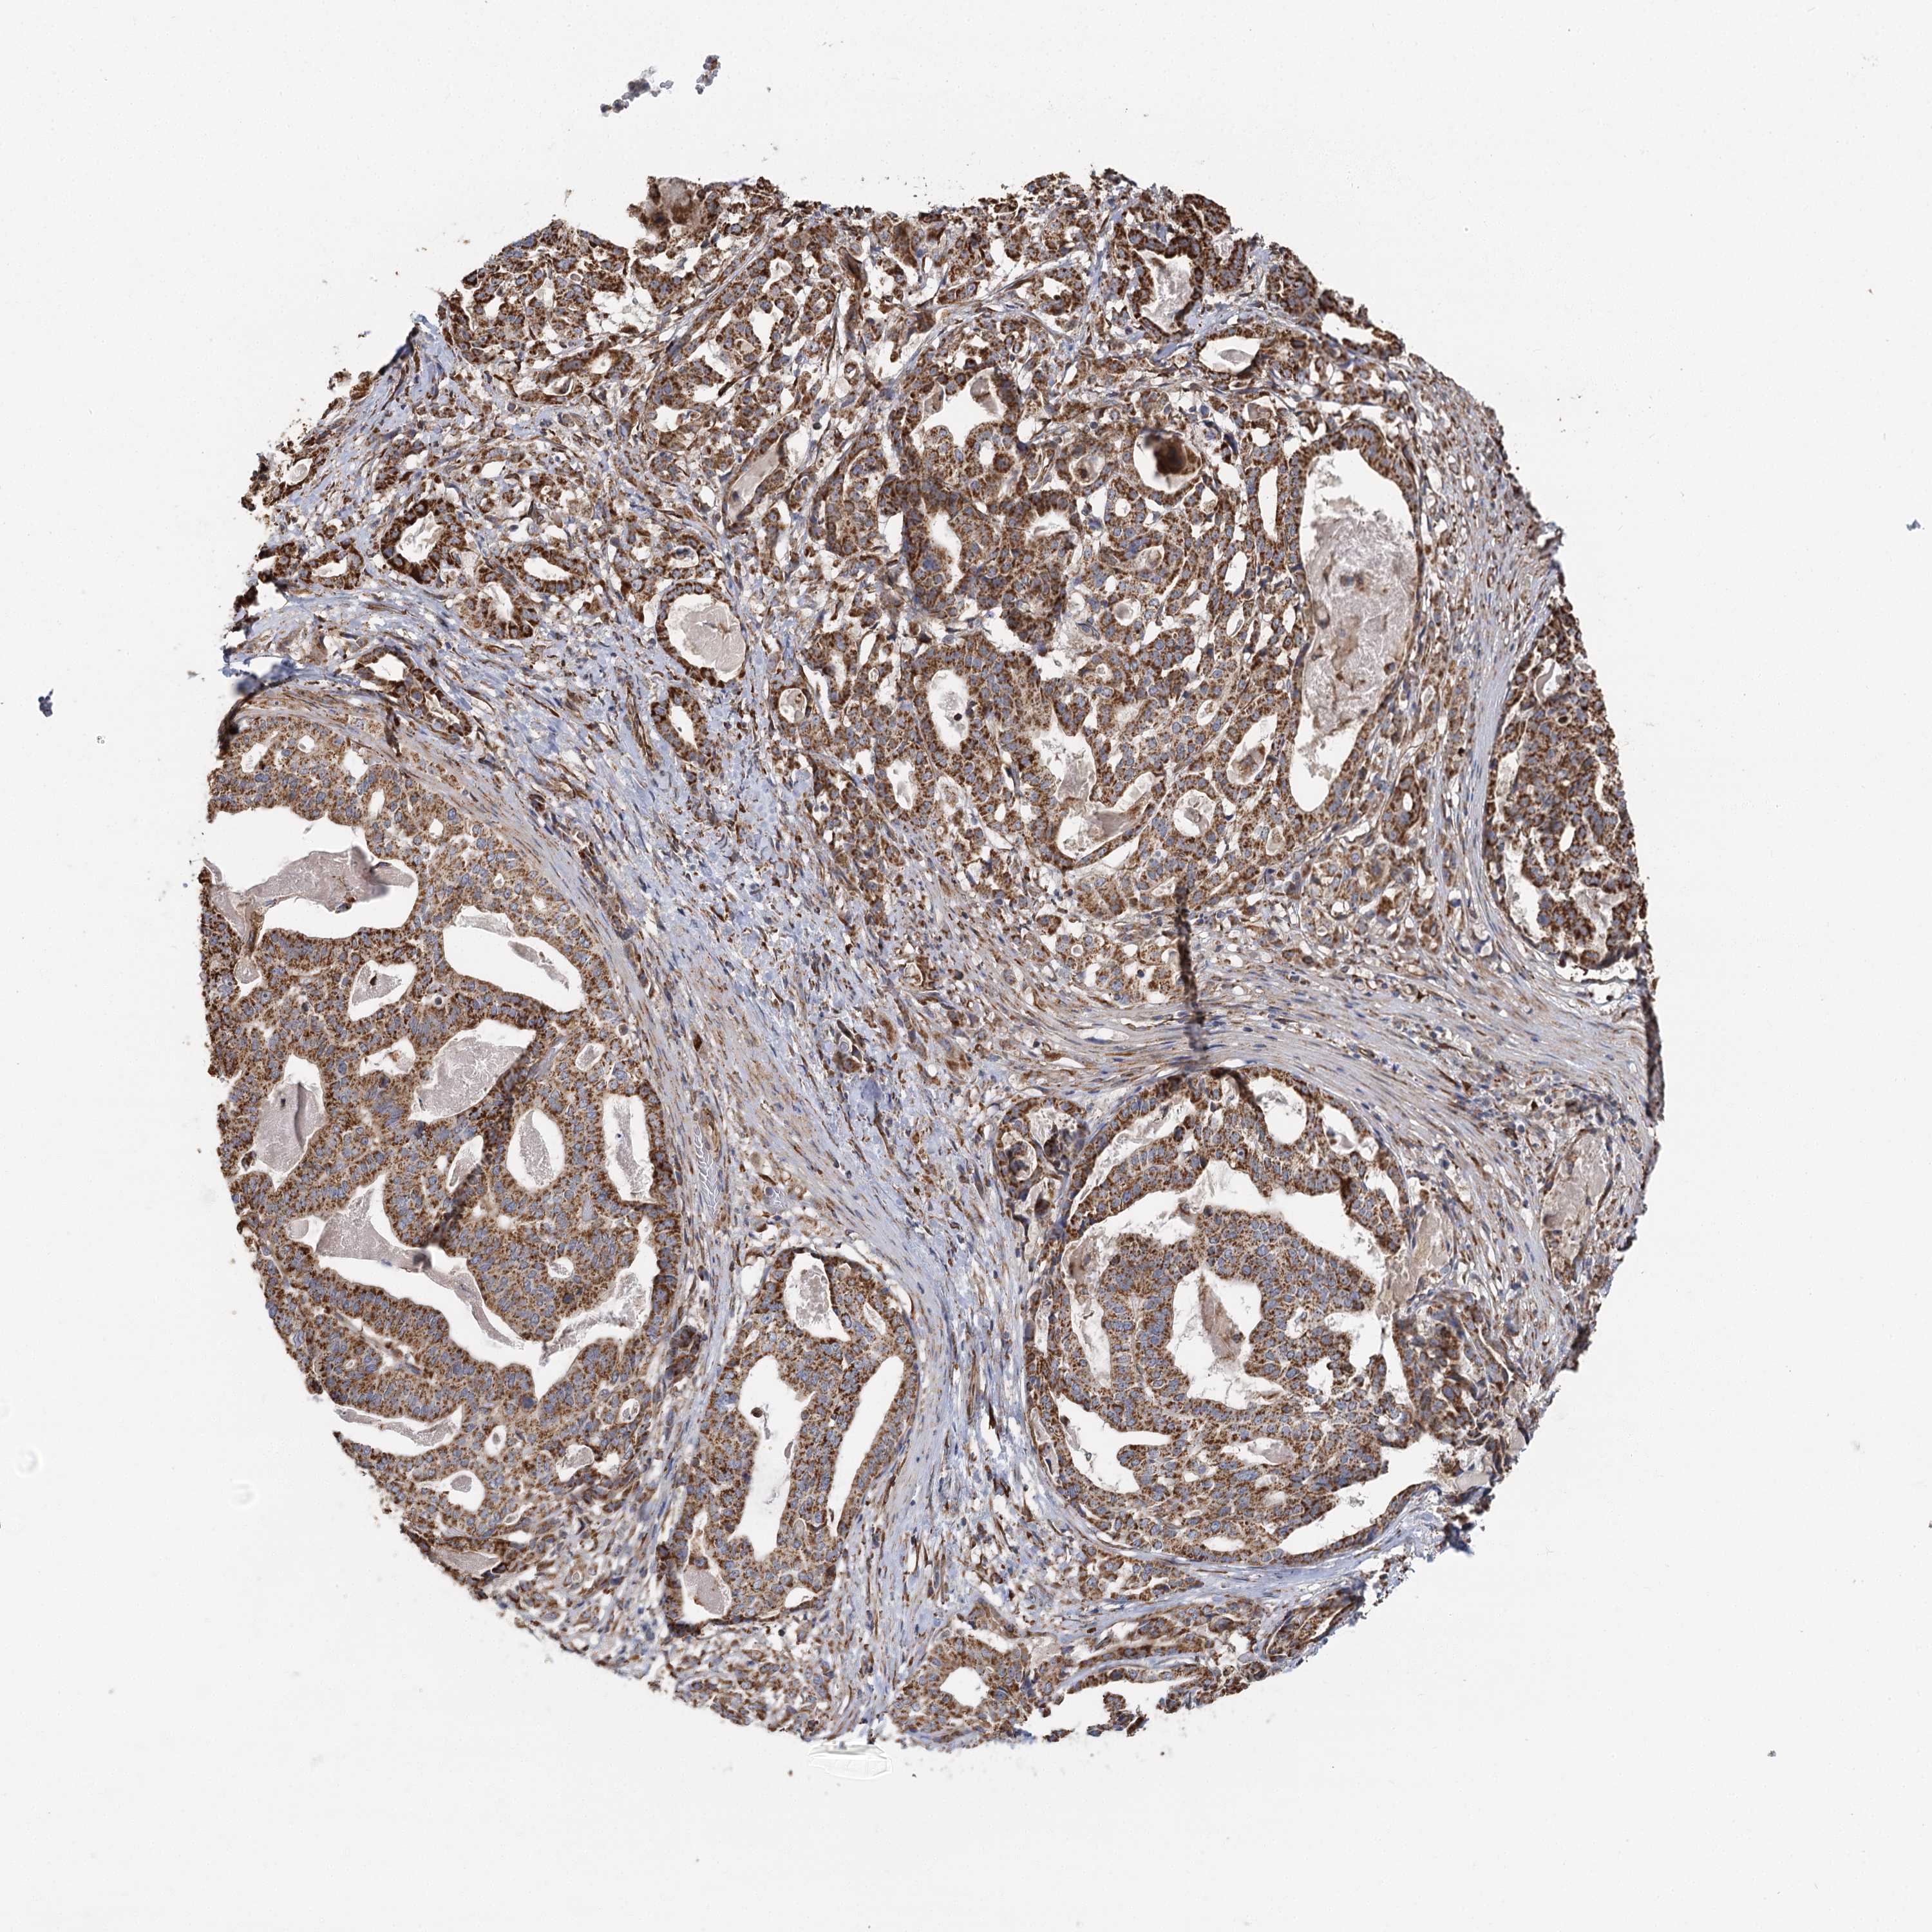

STOMACH CANCER - Protein expressioni

A mouse-over function shows sample information and annotation data. Click on an image to view it in a full screen mode. Samples can be filtered based on level of antibody staining by selecting one or several of the following categories: high, medium, low and not detected. The assay and annotation is described here.

Note that samples used for immunohistochemistry by the Human Protein Atlas do not correspond to samples in the TCGA dataset.

Antibody stainingi

Antibody staining in the annotated cell types in the current human tissue is reported as not detected, low, medium, or high, based on conventional immunohistochemistry profiling in selected tissues. This score is based on the combination of the staining intensity and fraction of stained cells.

Each image is clickable and will lead to virtual microscopy that enables deeper exploration of all samples and also displays staining intensity scores, fraction scores and subcellular localization as well as patient and tissue information for each sample.

Antibody CAB032830

Staining

High

Medium

Low

Not detected

Intensity

Strong

Moderate

Weak

Negative

Quantity

>75%

75%-25%

<25%

None

Location

Nuclear

Cytoplasmic/membranous

Cytoplasmic/membranous,nuclear

Adenocarcinoma, NOS

Adenocarcinoma, High grade